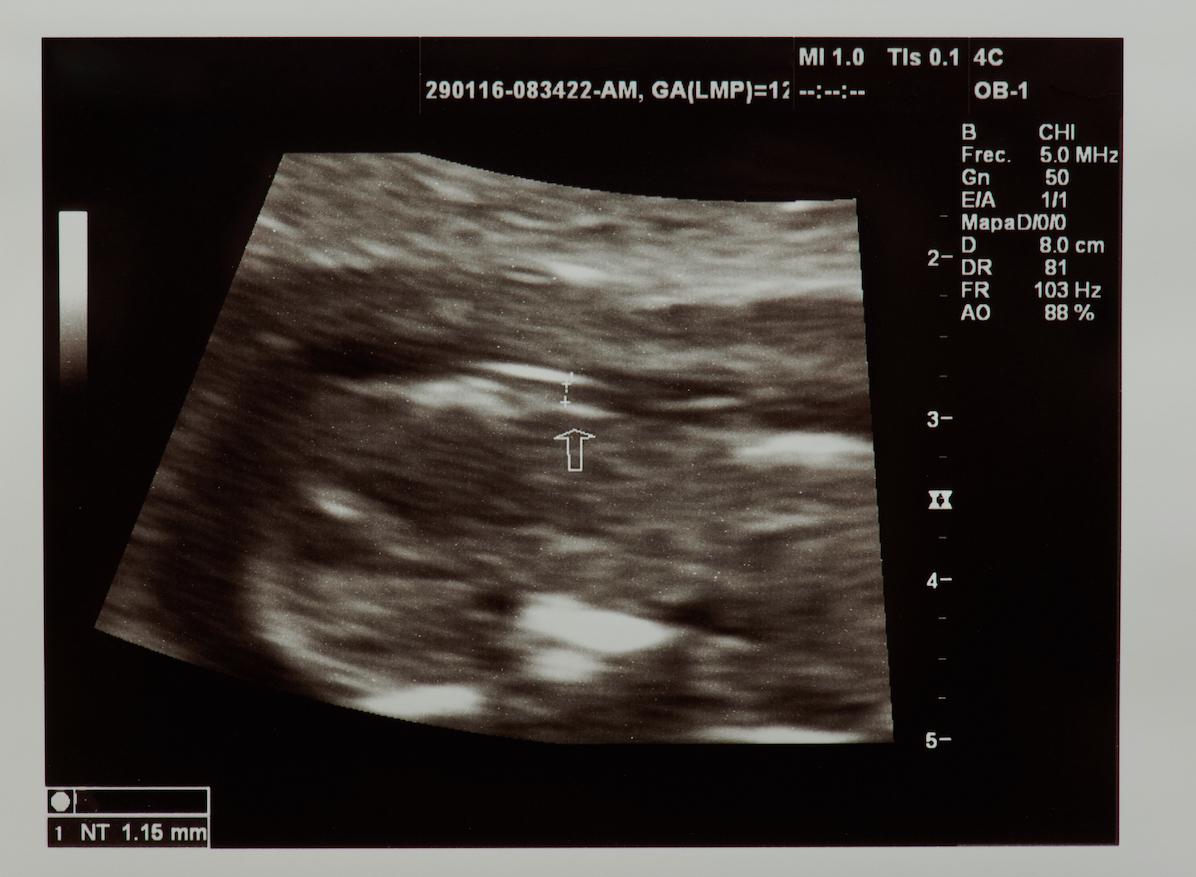

Tout commence en novembre 2016. À ce moment-là, Lucie, 27 ans, tombe enceinte. C’est en tout cas ce qu’elle croit puisqu’elle présente tous les signes d’une grossesse. “Puis un jour, je me mets à avoir très mal aux reins, assez pour que mon mari me conduise aux urgences, se souvient-elle. D'échographie en échographie, nous voilà avec un gynécologue et alors que je demande à mon mari s'il aperçoit le bébé sur le moniteur, le couperet tombe.” Le médecin lui annonce que le moniteur n’affiche pas de bébé mais une tumeur trophoblastique gestationnelle. Ce type de tumeur bénigne, également appelée grossesse molaire, se caractérise par la formation d’une masse de kystes appelée môle hydatiforme à la place d’un embryon normal.